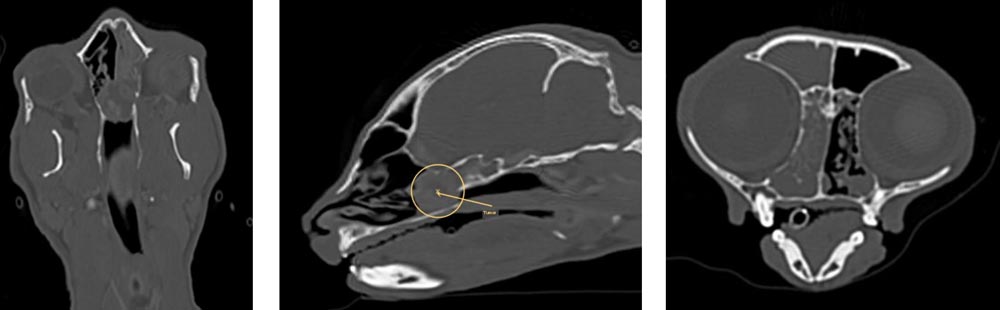

Dank des CTs können wir detaillierte 3D-Bilder von Organen und Geweben erstellen und so Erkrankungen erkennen, die mit herkömmlichen Methoden schwer sichtbar wären. Dies ist besonders hilfreich bei der Diagnose von Tumoren, Verletzungen oder Erkrankungen der inneren Organe und des Nervensystems.